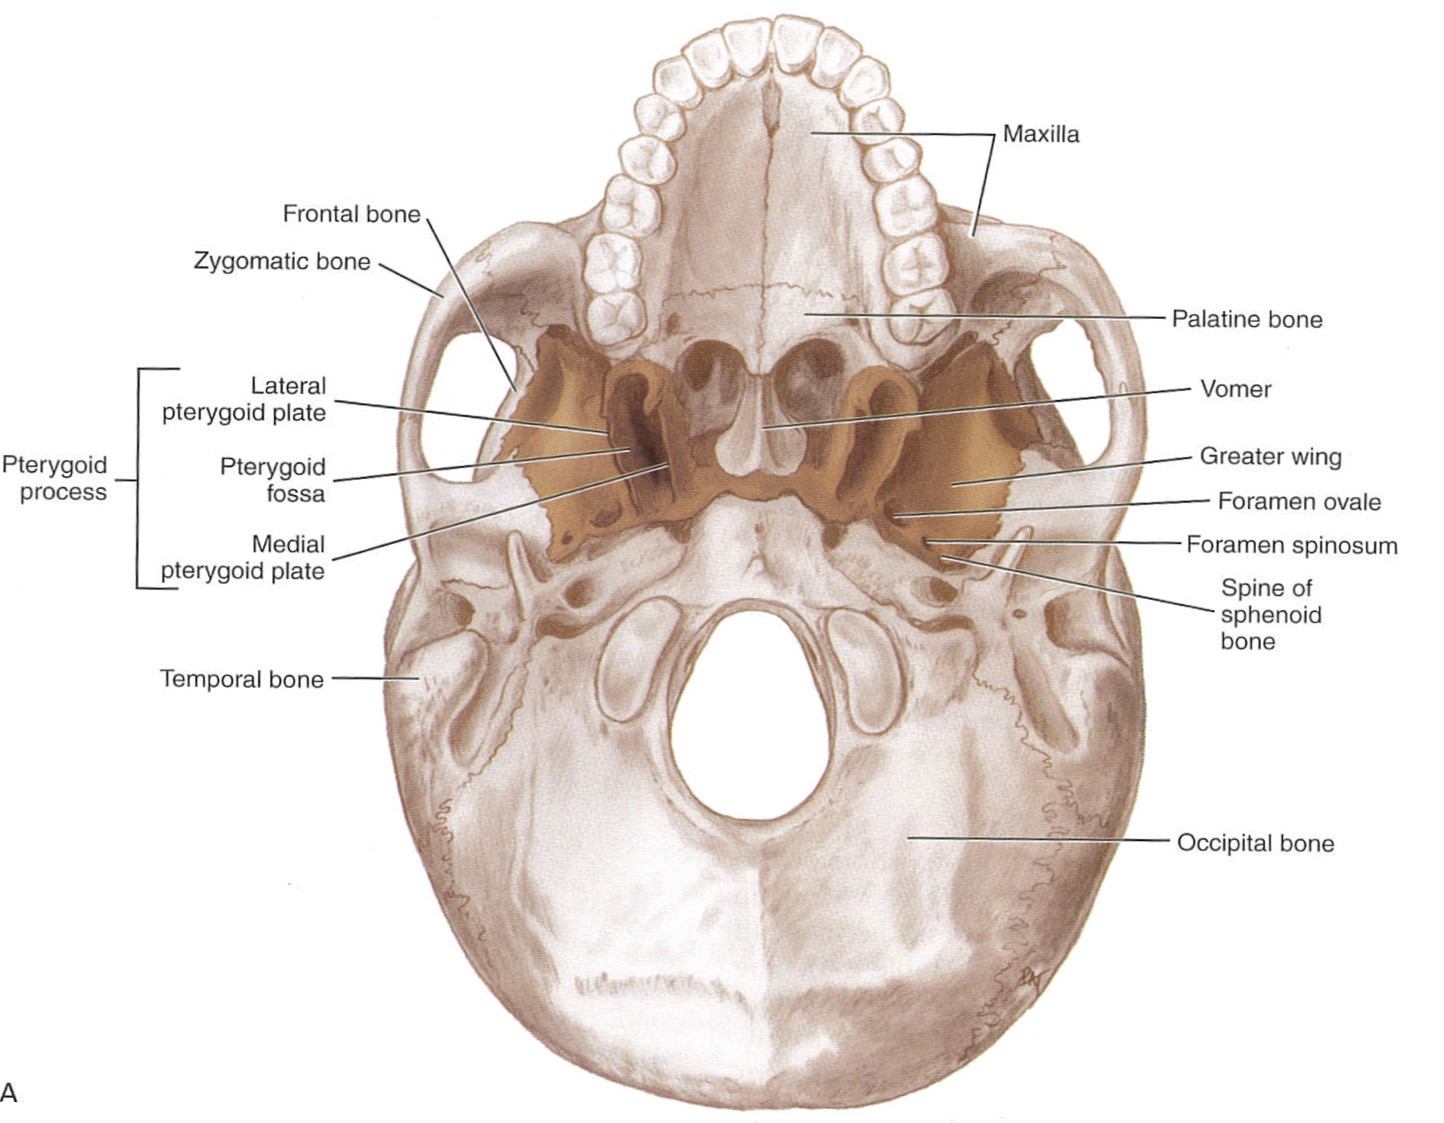

Sphenoid bone

-

pterygoid hamulus

-

Foramen rotundum

-

Foramen ovale

-

Foramen spinosum

-

Pterygoid canal

-

Foramen lacerum (破裂孔)

-

Optic canal

- CN II

- Ophthalmic a.

-

Sup. orbital fissure

- Ophthalmic n.(CN V1)/ v.

- CN III, IV, VI

相鄰骨

F, O, T, E, Pr, V, Z, Pl, Mx

Vomer

Maxillary bone

Palatine bone